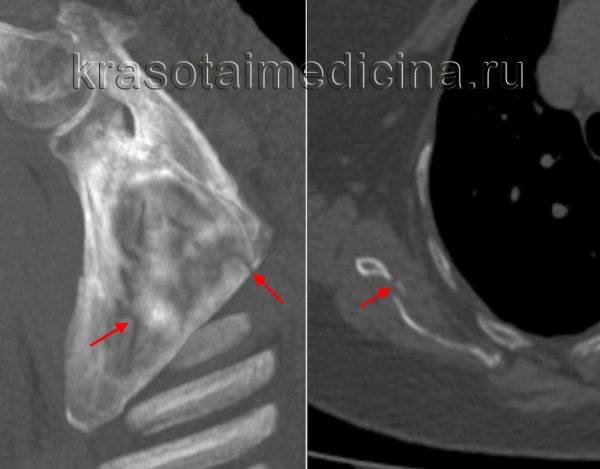

Перелом лопатки диагностируют по рентгенограммам. Сначала выполняют рентгенограмму в традиционной передне-задней проекции, затем, если возникает необходимость уточнить характер перелома, могут понадобиться рентгенограммы и в других проекциях.

Рентгенограмма: перелом шейки лопатки (красная линия) и основания акромиального отростка (зеленая линия).

Наиболее точная информация о характере перелома может быть получена с помощью компьютерной томографии с пространственной реконструкцией.